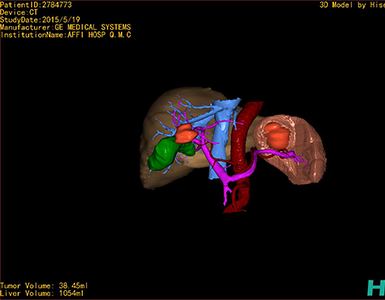

术前三维重建及手术方案设计:

将0.625mm双源薄层CT资料的静脉期和动脉期Dicom格式文件导入海信CAS系统。

通过调节窗宽窗位调整CT序号,对肿瘤,肝实质,胆囊,下腔静脉,肿瘤,肝动脉、门静脉及肝静脉等进行三维重建;系统自动计算肿瘤体积和肝脏体积。

模拟手术操作,自动计算切除肿瘤体积。肝脏体积为1054ml,肿瘤体积为38.45ml,肿瘤体积为肝脏体积的3.6%,通过比对50-60岁正常肝脏体积为1330.41±329.13 ml,通过术前模拟手术,精准判断切除后剩余肝脏体积能耐受,避免肝衰竭发生。

术前三维重建:

重建图片